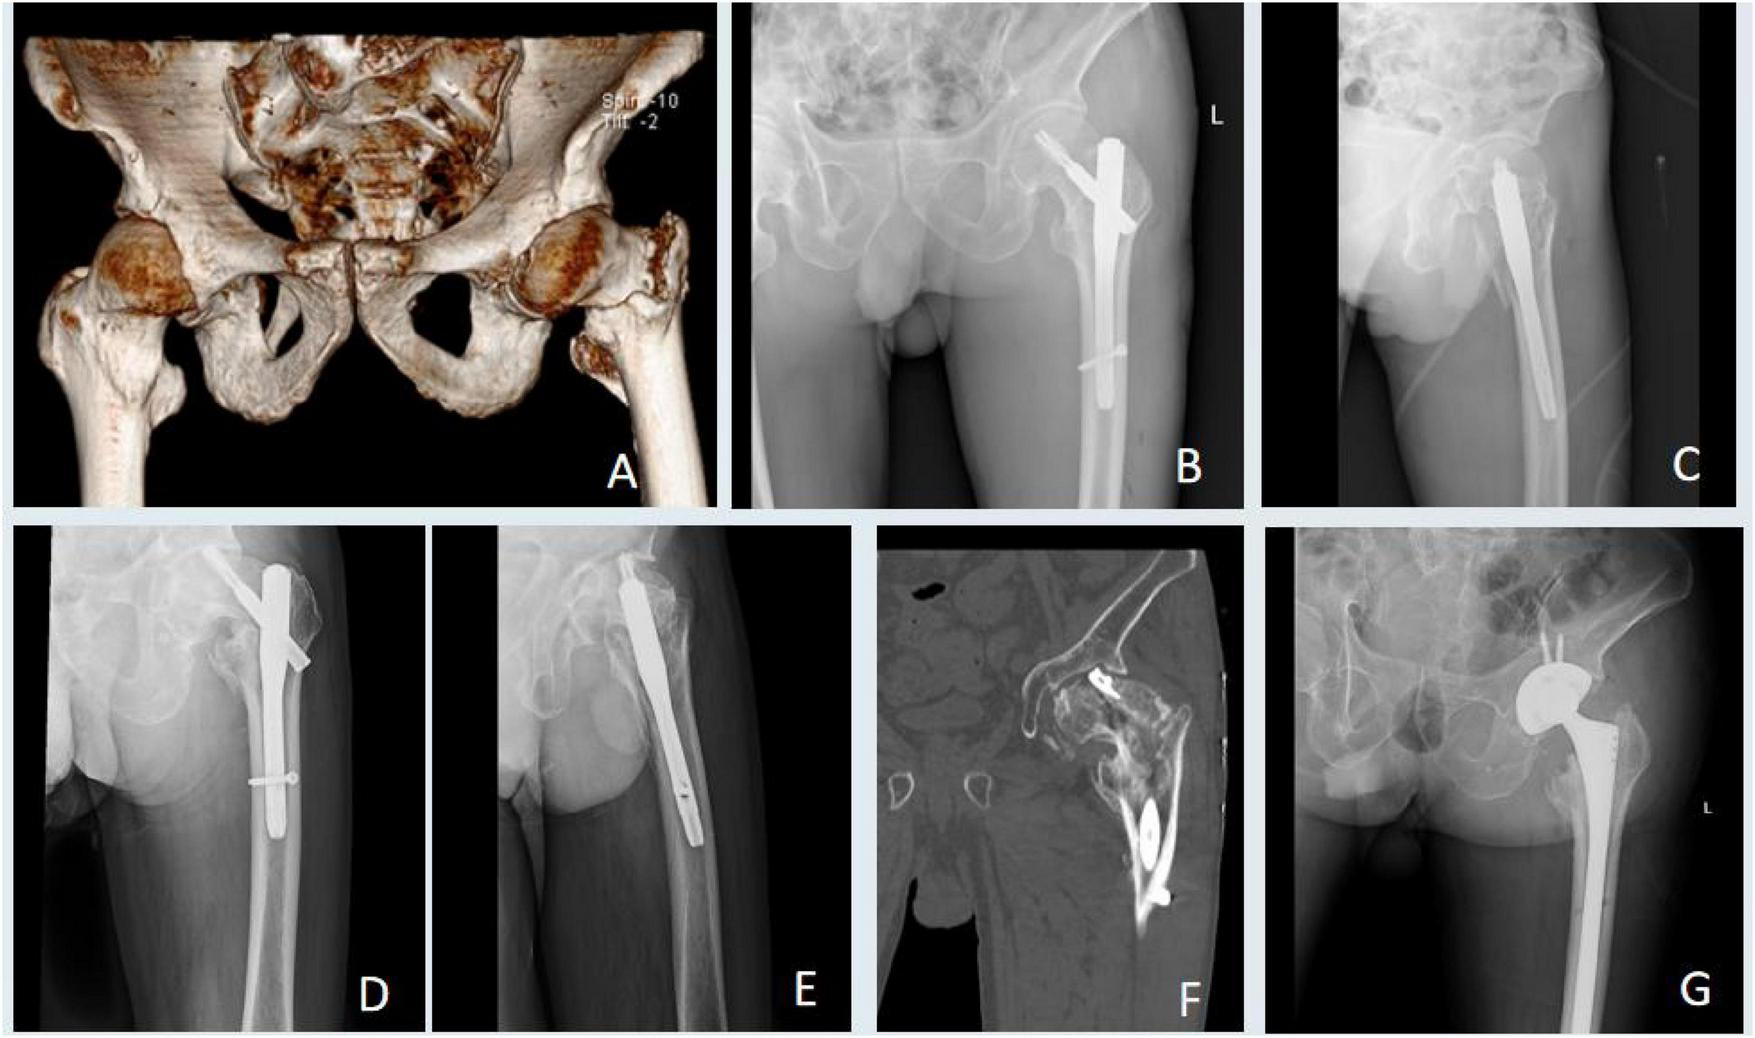

Management of a major implant failure in a patient from the low grip strength group. (A) Preoperative radiograph showing a left intertrochanteric fracture. (B,C) Postoperative radiographs at 2 days. (D–F) Radiographs at 6 months revealing implant cut-out and failure. (G) Radiograph after implant removal and subsequent total hiparthroplasty.

Functional outcome assessment